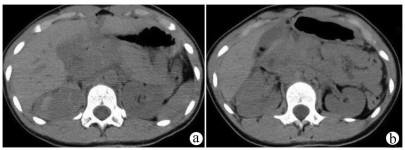

A preliminary study on percutaneous transhepatic drainage combined with sequential percutaneous nephroscopy in treatment of refractory liver abscess

Changhu DUAN, Xiaochen LIU, Jianlong DING, Jianfeng DUAN, Xirong ZHAO, Fan YANG, Ling WU, Lifei ZHAO, Sheng TAI

2021, 37(11): 2622-2625. DOI: 10.3969/j.issn.1001-5256.2021.11.026

Abstract(1123) HTML (227) PDF (2925KB)(75)

Abstract:

Objective  To investigate the clinical effect of percutaneous transhepatic drainage combined with sequential percutaneous nephroscopy for necrosectomy and drainage in the treatment of refractory liver abscess after transcatheter arterial embolization (TACE).  Methods  A retrospective analysis was performed for three patients with refractory liver abscess after TACE in The Affiliated 3201 Hospital of Xi'an Jiaotong University School of Medicine from January 2018 to December 2020, and among the three patients, one had the formation of liver abscess after TACE for hepatic metastases after pancreaticoduodenectomy, one had liver abscess after repeated TACE for massive hepatocellular carcinoma, and one had secondary liver abscess after TACE for traumatic hepatic rupture. All three patients received percutaneous transhepatic drainage and sequential percutaneous nephroscopy for the treatment of refractory liver abscess, and their specific treatment process was summarized.  Results  All three patients were diagnosed with refractory liver abscess based on CT, routine blood test, procalcitonin, blood culture, and clinical manifestation. Percutaneous transhepatic catheterization under the guidance of conventional ultrasonography or CT and effective antibiotics had an unsatisfactory therapeutic effect, and after sequential percutaneous nephroscopy was performed for necrosectomy and drainage, liver abscess was cured and the patients had good prognosis.  Conclusion  For refractory liver abscess after TACE, when routine puncture treatment has an unsatisfactory therapeutic effect or a patient cannot tolerate surgical operation, percutaneous transhepatic drainage combined with sequential percutaneous nephroscopy is safe and effective in the treatment of refractory liver abscess.